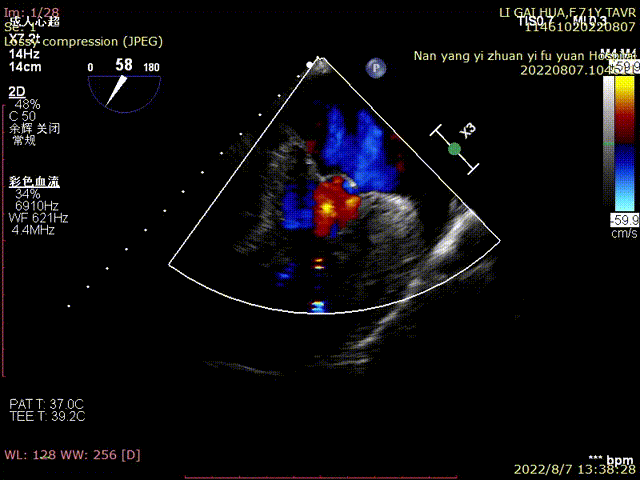

术前TEE超声:

超声明确瓣膜位置

超声评估

瓣膜释放后超声评估:

术中,心外体外循环科郑军医师全程待命。彩超室张俊鹏老师全程跟台,术后行超声探查未见瓣周漏,血压改善。